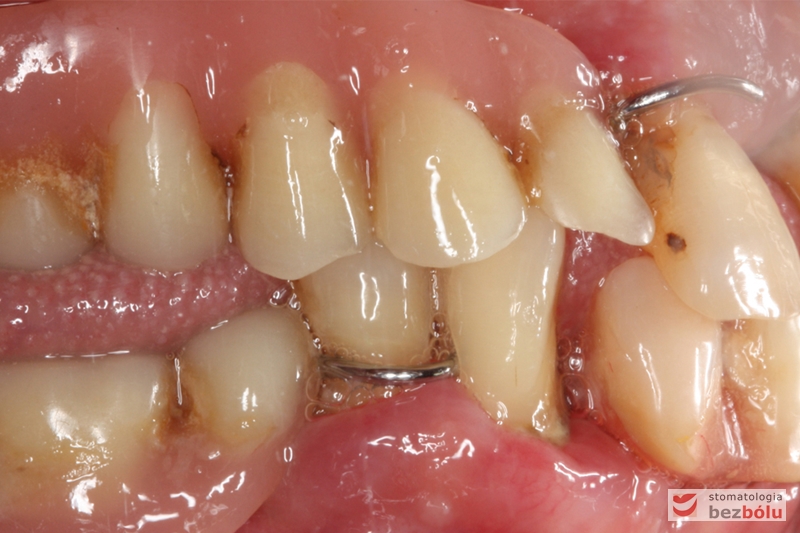

Stan wyjściowy - bez protez, liczne braki zębowe i po 2 nierokujące zęby w szczęce i żuchwie

Stan wyjściowy – bez protez, liczne braki zębowe i po 2 nierokujące zęby w szczęce i żuchwie